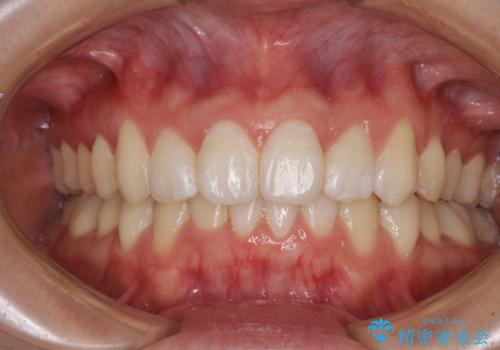

前歯のデコボコと下顎の八重歯 インビザラインによる矯正治療

担当医 藤巻太一朗